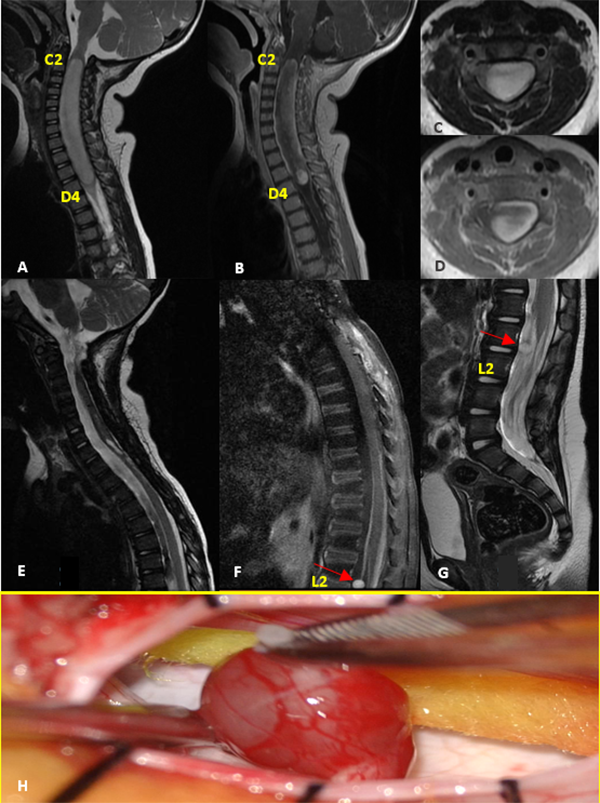

Paciente sexo femenino que a los 9 meses se le realizó exéresis total de tumor intramedular cervico-dorsal (C1-D4) en otra institución, cuyo diagnóstico anatomopatológico informó ependimoma de alto grado, por lo que completó tratamiento adyuvante con quimioterapia (6 ciclos de cisplatino, etopósido, vincristina y ciclofosfamida según protocolo HeadStart II), con posterior trasplante autólogo de médula ósea. Inicialmente debutó con falta de adquisición en las pautas motoras asociado a paresia de miembros superiores. En el postoperatorio evolucionó con cuadriparesia e hidrocefalia requiriendo colocación de shunt ventrículo peritoneal. A los 2 años de vida en los controles de RM se evidencia marcado refuerzo postcontraste y engrosamiento de las raíces de la cauda equina, destacándose a la altura de L2, una imagen nodular con intensa captación de contraste, que medía 6 x 5 x 6 mm aproximadamente. Se realizó la resección completa de la lesión. La anatomía patológica reveló glioma difuso de bajo grado (Grado II de la OMS) (Figura 4).

Figura 4:

Glioma Difuso de Bajo Grado. A-D: RM prequirúrgica T1 con contraste y T2 cortes axiales y sagitales. E-G: RM postquirúrgica alejada que evidencia resección completa de tumor cervical con lesión metastásica nodular a nivel de L2 (flecha roja). H: Imagen intraoperatoria de la lesión.